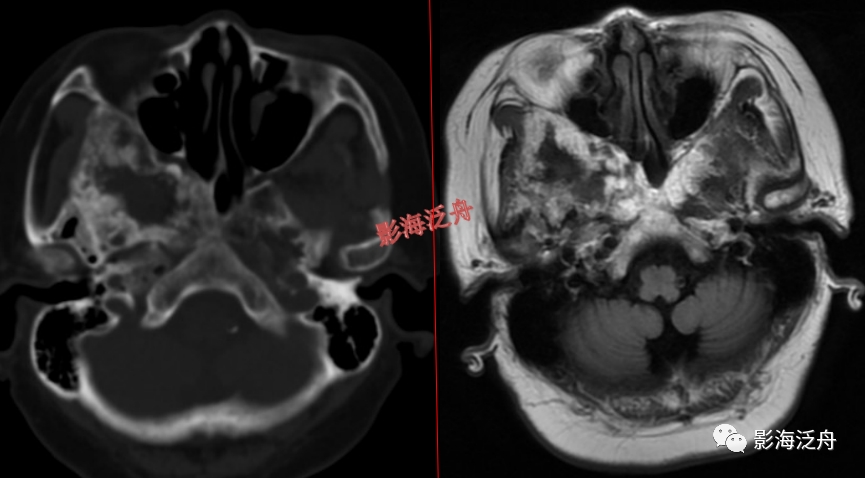

蝶骨骨纤维异常增殖症(红箭头),病灶内部可见特征性的囊变区(黄箭)。蝶骨的病变在MR上识别起来更为困难,因为蝶骨位于颅底部,此处骨骼、肌肉、脂肪等多种组织成分混杂,导致正常情况下也看起来非常乱。不要着急,慢慢学。

左侧顶骨骨纤维异常增殖症。病灶位于左侧顶骨板障区,局部骨质呈膨胀性改变,病灶边缘骨质硬化,呈明显低信号(红箭头),内部可见大片状絮状结构(黄箭)以及局灶性的玻璃样变性区(绿箭头)。